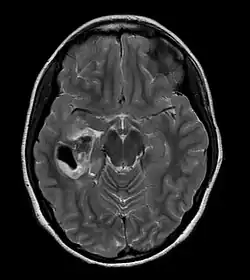

Pleomorphic xanthoastrocytoma

Pleomorphic xanthoastrocytoma (PXA) is a brain tumor that occurs most frequently in children and teenagers. At Boston Children's Hospital, the average age at diagnosis is 12 years.[1]

Pleomorphic xanthoastrocytoma usually develops within the supratentorial region (the area of the brain located above the tentorium cerebelli). It is generally located superficially (in the uppermost sections) in the cerebral hemispheres and involves the leptomeninges. It rarely arises from the spinal cord.

These tumors are formed through the mitosis of astrocytes. They are found in the area of the temples, in the brain's frontal lobe or on top of the parietal lobe. In about 20% of cases, tumors exist in more than one lobe.